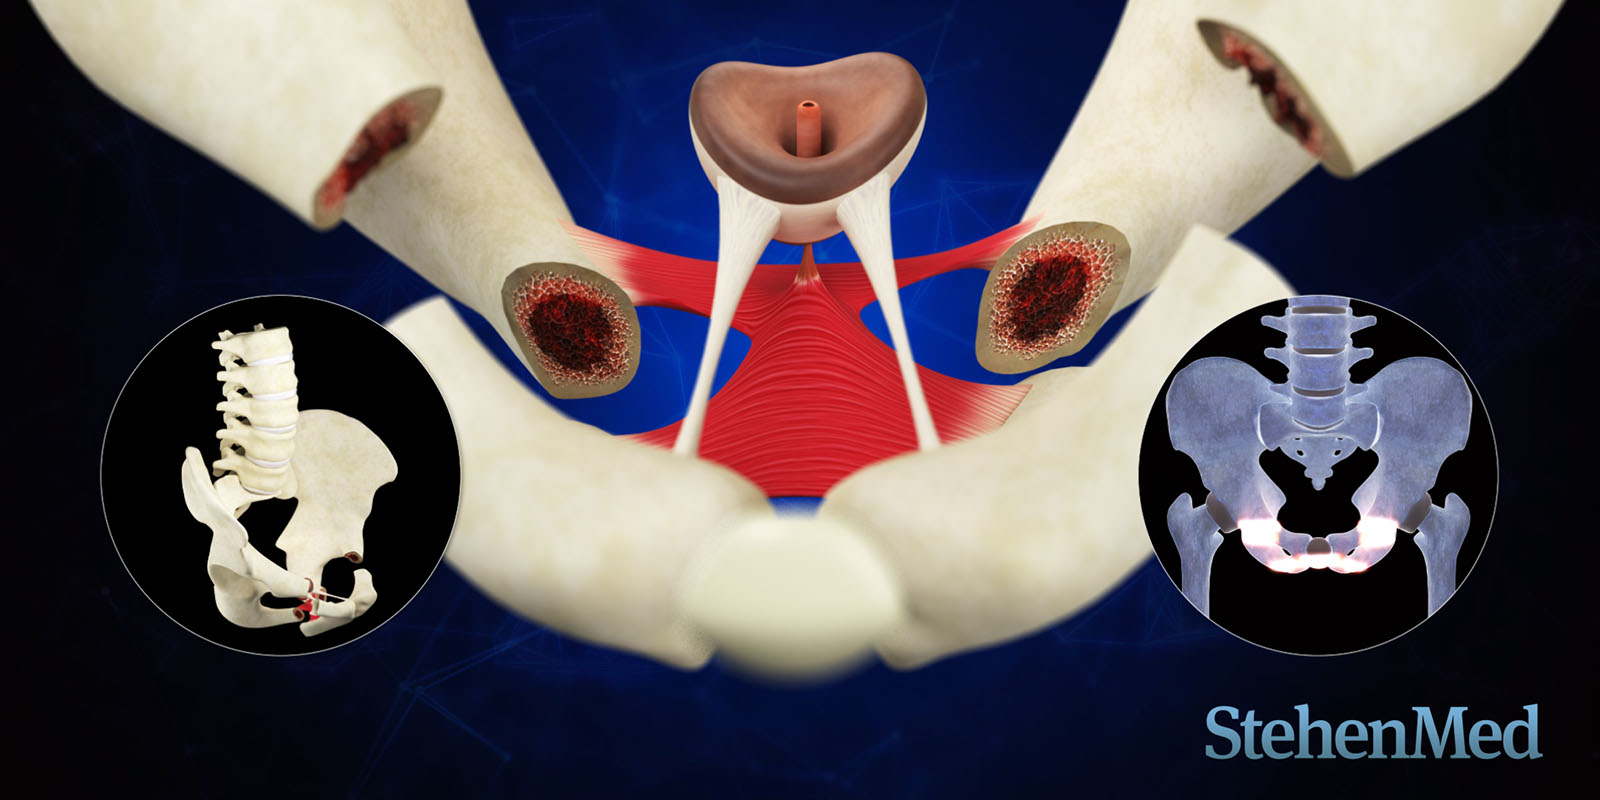

Visualización de eventos accidentales que provocan la lesión y mecanismos internos del trauma.

Categoría: Animación 3D - Traumas

Conceptos clave: Lesiones, Accidentes, Pelvis, Uretra

Duración: 2m 34s